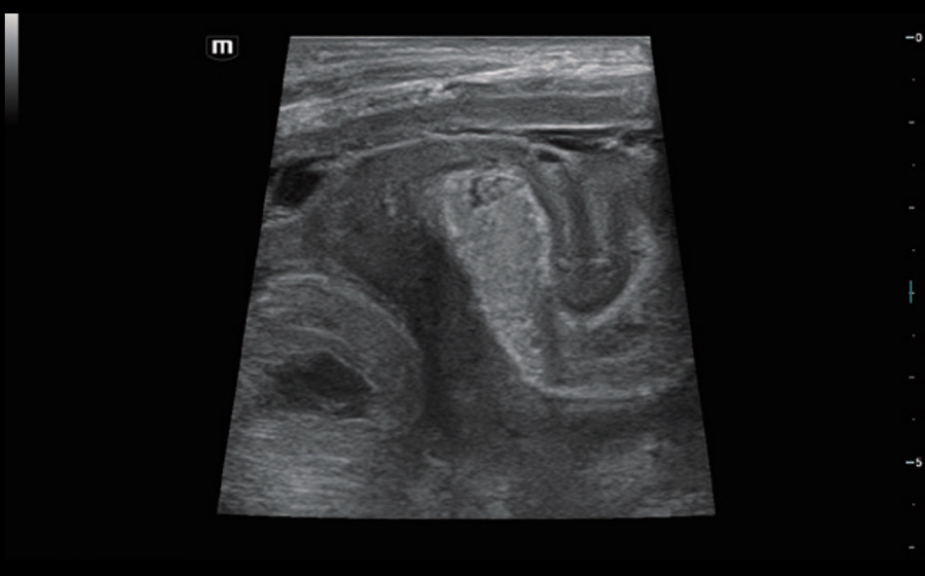

Innovative Stiffness Assessment: HiFR STE

Up to 10 times faster frame rate with smooth STE imaging display

More sensitive motion detection for better stability and greater accuracy

HiFR STE of breast cancer

Innovative Stiffness Assessment: HiFR STE

Up to 10 times faster frame rate with smooth STE imaging display

More sensitive motion detection for better stability and greater accuracy

HiFR STE of breast cancer